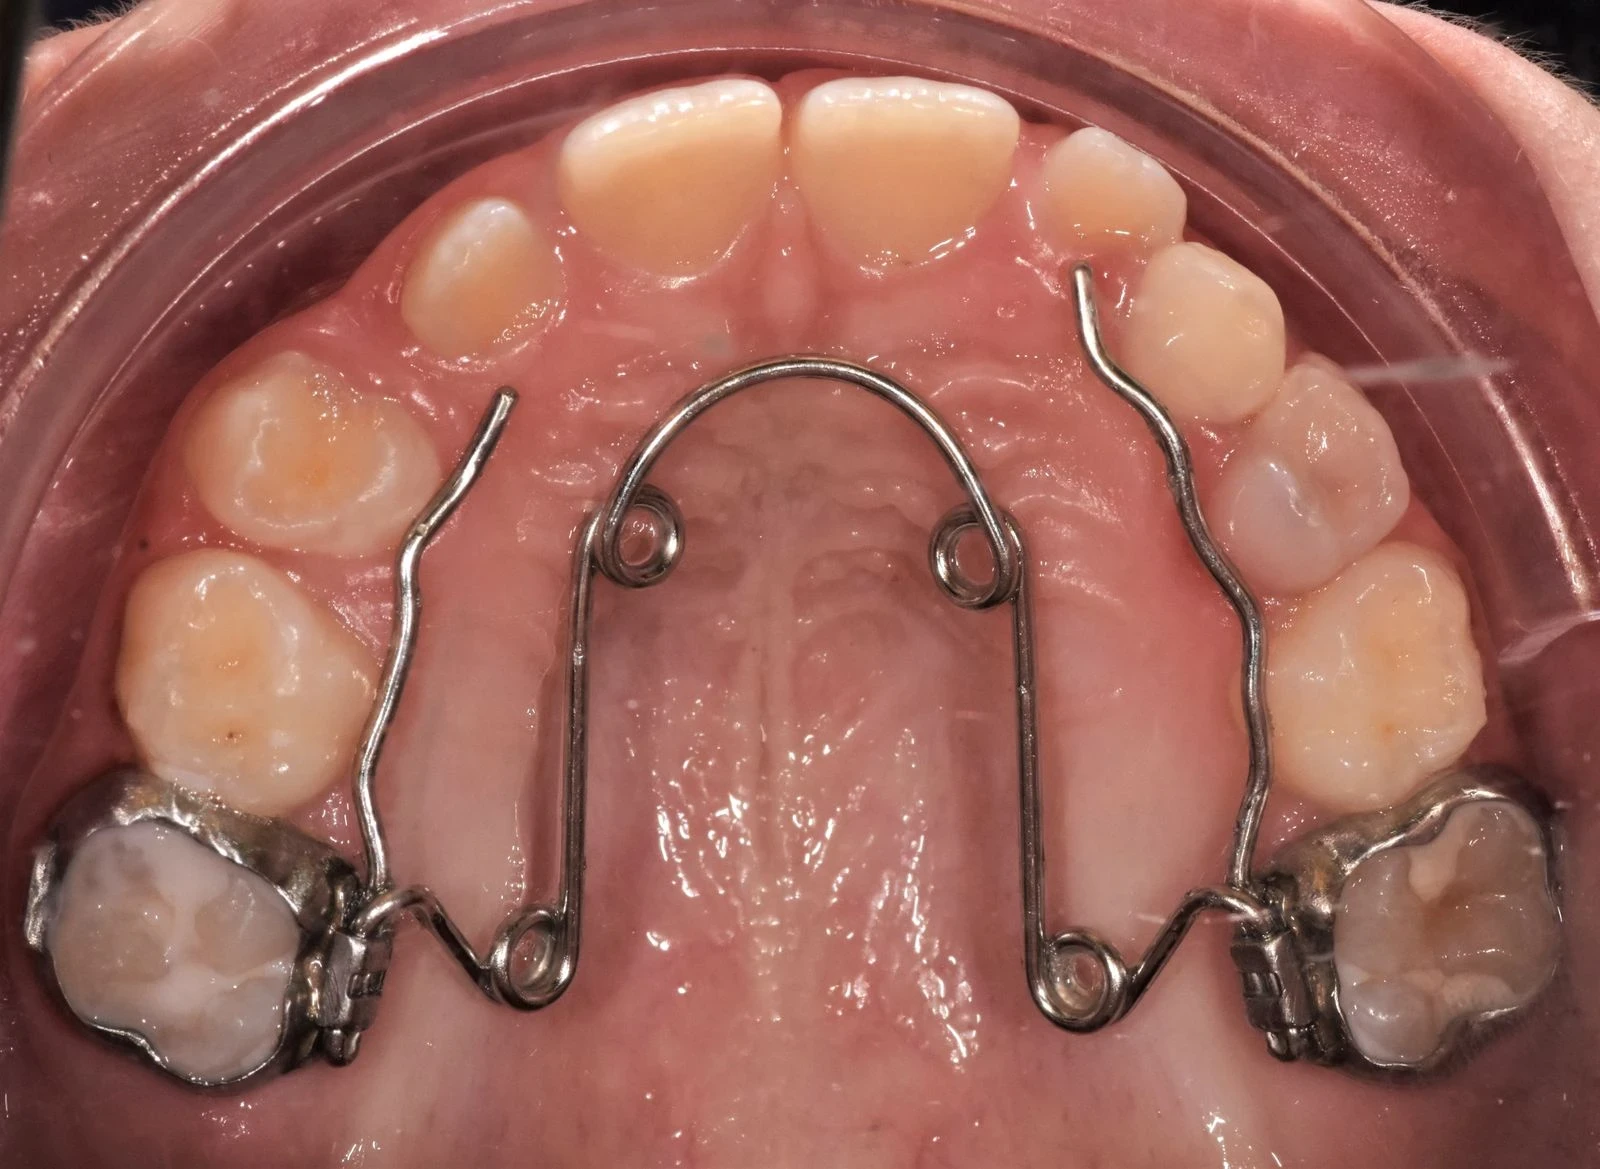

Contentions

Qu'est-ce que la contention dentaire et à quoi sert-elle ?

La période de contention dentaire est tout aussi importante que la période active du traitement d’orthodontie.

À la fin d'un traitement, il est nécessaire de consolider les résultats obtenus afin d’éviter que les dents ne se déplacent à nouveau. En effet, après le port d'un appareil dentaire, qu'il s'agisse de bagues classiques, d'un appareil lingual ou même d'aligneurs transparents, le risque de récidive est important, en raison de multiples facteurs tels que :

Il s'agit donc d'une période incontournable, qui va permettre de maintenir le bon alignement des dents, obtenu à l’issue du traitement orthodontique actif.

On distingue deux types d'appareils de contention :

Les contentions fixées : il s’agit de fils de contentions que l’on colle sur les faces internes des dents.

Les contentions amovibles : il s’agit de gouttières de contention, similaires aux gouttières d’alignement, mais dont la rigidité est différente et qui ne se portent que la nuit.